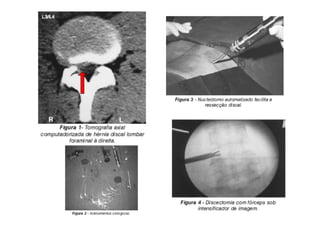

Prolapsos Discais Torácicos

• Os prolapsos discais na coluna torácica são raros e têm várias

apresentações, muitas vezes com um quadro clínico que dá margem a

muitas dúvidas.

Pode haver dor no peito em faixa, escoliose, distúrbios neurológicos

bizarros com alterações de temperatura periférica, alteração dos reflexos

e fraqueza das extremidades inferiores.

Alguns são erroneamente diagnosticados com esclerose múltipla ou ELA -

esclerose lateral amiotrófica.

• Podem ser diagnosticados por RM e tratados por excisão transtorácica.

Hérnia Discal Torácica Baixa

PROVOCANDO lombociatalgia =/= Hérnia Discal Lombar

Relação das raízes nervosas torácicas com os corpos vertebrais

torácicos

08/12/2015 Dr. José Heitor Machado Fernandes 226

Hérnia discal

Torácica entre

T9-T10 pode

dar dor irradia-

da à região lombar

Nas lombalgias

sem lesão aparente

na coluna lombar,

pesquisar hérnia

discal em Coluna

Torácica !

Fonte: Prof. Dr. Tarcisio EP de Barros Filho

Hérnia Discal Torácica

Tratamento Cirúrgico da Hérnia Discal Torácica

Cirurgia Toracoscopia Vídeo Assistida

VATS